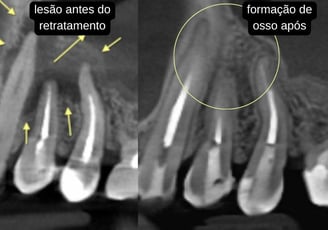

Retratamento endodôntico

Reintervenção em dentes que já possuem canais tratados, mas que não foram bem sucedidos.